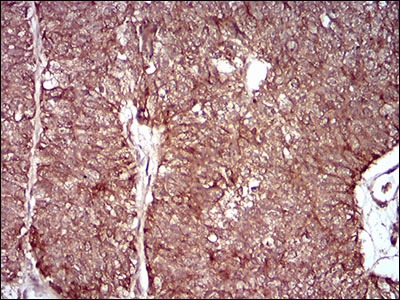

3. Immunohistochemical analysis of paraffin-embedded human ovarian cancer tissue using anti-MMEL1 antibody. Counter stained with hematoxylin.

4. Immunohistochemical analysis of paraffin-embedded human cervical cancer tissue using anti-MMEL1 antibody. Counter stained with hematoxylin.